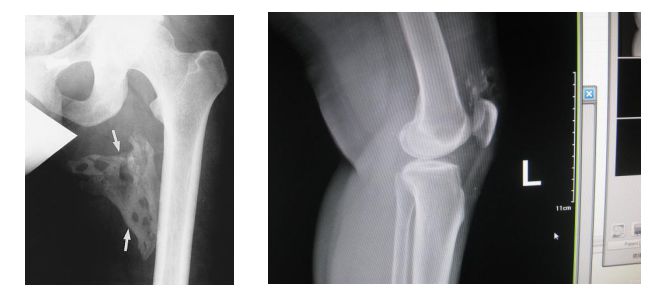

其临床表现有两个特点:先天性拇指畸形、进行性软组织异位骨化。其中前者为该病最早的特征表现,几乎所有的患者都会发生。

异位骨化多发生于肌腱、韧带、筋膜和骨骼肌等处,其蔓延特点为从头向尾、从背侧向腹侧、从中线向四肢发展,骨化可由外伤、感染和手术等诱发加速。

其他辅助检查:X 线照片显示肿物的软组织当中有分散钙化影。过一段时间,急性期的症状和体征消失后,肿物变小,钙化影也缩小,但密度增高。X 线片上可见柱状或不规则形态的团块状不同密度的骨化阴影,可与骨骼相连,也可完全游离。骨骼呈现失用性萎缩。

(FOP患者的X光片,异位骨化影响整个骨骼系统的形态,除局部的变形之外,脊柱也无法伸直)